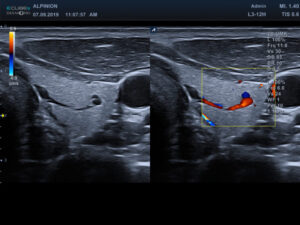

Ultrasonograf Alpinion E-CUBE 8 to jeden z najczęściej wybieranych systemów do badań endokrynologicznych

Wybrane obrazy kliniczne